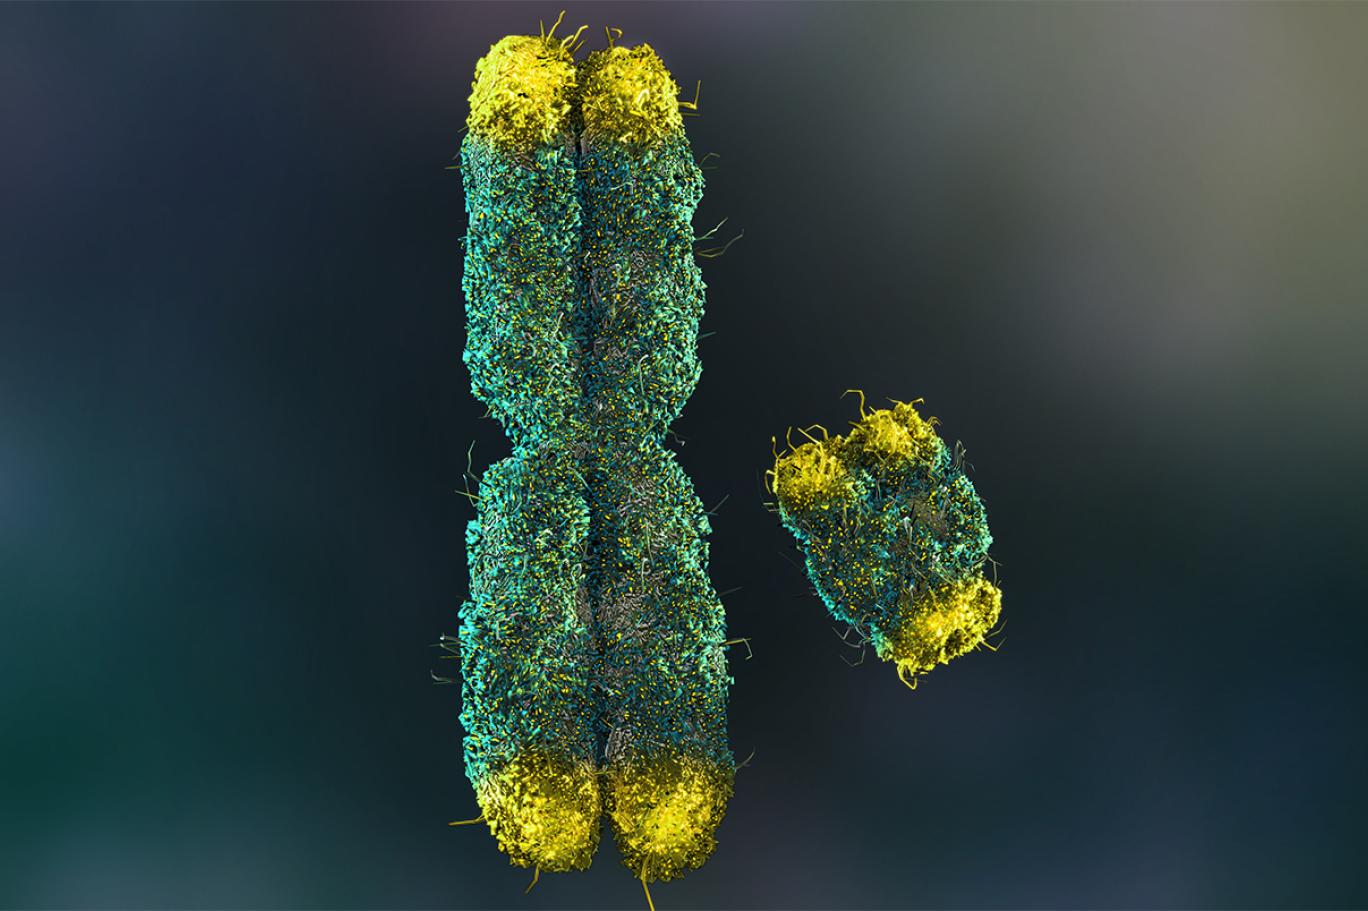

تبين أن فقدان الكروموسوم "واي" [يضم جسم الإنسان مجموعة من 23 زوجاً من الكروموسومات، يختص إثنان منهما بالمواصفات الجنسية، هما "واي" للصفات الذكرية و"إكس للأنثوية] في خلايا الدم لدى الرجال مع تقدمهم في العمر يؤدي إلى خلل في وظائف القلب والوفاة بسبب أمراض القلب والأوعية الدموية، وذلك وفق دراسة حديثة ربما تقود إلى علاجات جديدة لأمراض القلب.

نشرت الدراسة الجديدة في مجلة "ساينس"Science ، وقد وجدت أن الرجال الذين يخسرون الكروموسوم "واي"، علماً أن هذه الحالة الصحية تسمى "فقدان فسيفساء الكروموسوم واي" mosaic Loss Of Y (اختصاراًmLOY )، الموجود في خلايا دمهم البيضاء، يرتفع لديهم أيضاً خطر الوفاة نتيجة أمراض القلب التي تعد السبب الأكثر شيوعاً للوفيات.